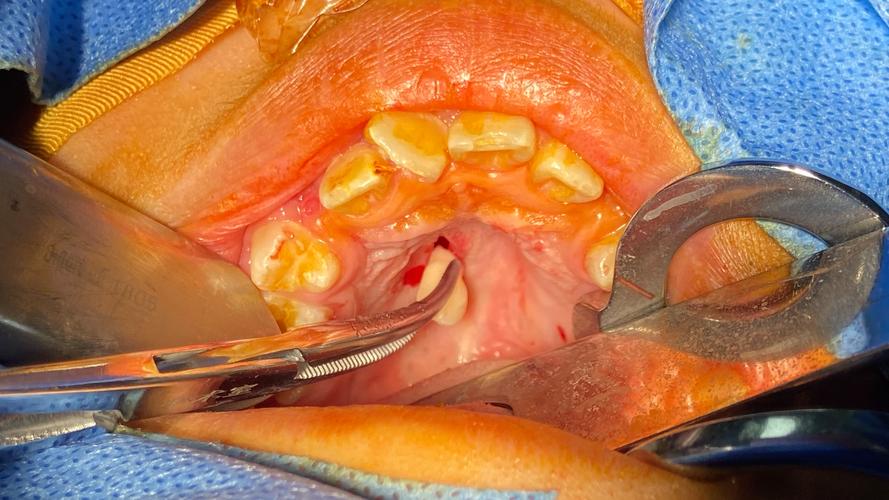

暴露与松动多生牙

- 暴露牙冠: 去除足够骨质后,暴露多生牙的牙冠。

- 微创器械应用:

- 微创拔牙挺: 使用薄而锋利的挺(如Molt挺、三角挺、直挺),轻柔、精细地插入牙冠与骨壁之间的间隙,利用楔力和轻微的旋转力进行松动。避免使用杠杆力,防止损伤邻牙或骨壁。

- 分根技术: 如果多生牙牙根弯曲、分叉或与邻牙粘连,可能需要使用高速手机或超声骨刀在根分叉处或靠近牙根处进行分根,将其分成2-3个部分分别拔除,这能大大降低拔除难度和风险。

- 根挺: 对于已松动或部分脱出的牙根,使用根挺小心地将其挺出或拔出。

取出多生牙

- 三角钳/取根钳: 使用精细的取根钳夹住已松动或分根后的牙体部分,轻柔、持续地旋转、牵引拔除,避免暴力摇晃。

- 避免反复操作: 一旦器械到位,应争取一次成功取出,减少对周围组织的反复刺激和损伤。